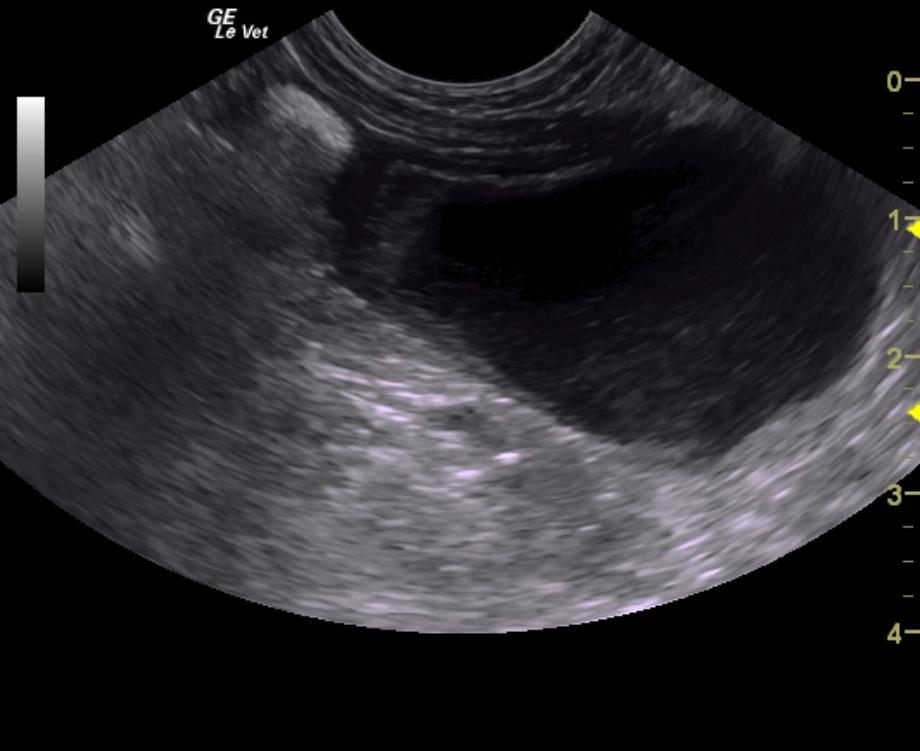

A 14-year-old neutered male Poodle dog was presented for evaluation of chronic hematuria with a history of calcium oxalate calculi and evidence of urinary tract infection.